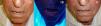

En el caso de los CBC perioculares o de localización en los párpados, al igual que sucede con la TFD, podría ser una contraindicación absoluta el empleo de imiquimod para su tratamiento. Sin embargo, existen muchas publicaciones cuyos resultados ofrecen la oportunidad de utilizarlo en casos seleccionados115–119 (fig. 8). Son especialmente interesantes dos trabajos de García-Martín et al118 y de Cannon et al119. En el primero obtienen una respuesta clínica e histológica completa en los 15 CBC perioculares tratados con imiquimod, con muy buenos resultados estéticos. En el segundo realizan una revisión de los efectos secundarios de los 47 pacientes que recibieron tratamiento con imiquimod de sus tumores perioculares. El efecto secundario más frecuente fue una conjuntivitis de intensidad media en 11 pacientes, y todos los efectos secundarios se resolvieron tras el cese del tratamiento con imiquimod sin ningún efecto secundario residual.

Carcinoma basocelular superficial en el párpado inferior del ojo derecho tratado con imiquimod. A. Previo al tratamiento. B. Reacción local y conjuntivitis leve en la semana 3 de tratamiento. C. Reacción local y conjuntivitis leve en la semana 6 de tratamiento. D. Respuesta clínica y resolución de la conjuntivitis un mes después de finalizar el tratamiento con imiquimod.